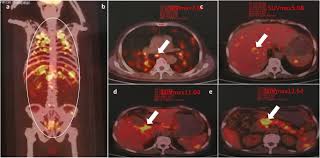

Concomitant active tuberculosis in nsclc (tblc) resembles locoregional immunotherapy of tumor cell vaccine;

Difference between lung cancer and tuberculosis. This growth can spread beyond the lung by the process of metastasis into nearby tissue or other parts of the body. Selection of the most suitable tests for detection of m. However, this can also occur with tuberculosis or a pulmonary embolism. Concomitant active tuberculosis in nsclc (tblc) resembles locoregional immunotherapy of tumor cell vaccine; Primary tuberculosis clinical forms the primary site of infection in the lungs is called the ghon focus. Living with advanced breast cancer. Symptoms of tuberculosis and lung cancer are overlapping and it is difficult to differentiate without the histopathological report. When people with lung tb cough, sneeze or spit, they propel the tb germs into the air. Lung cancer and pulmonary tuberculosis (tb) comorbidity is a clinical problem that presents a challenge for the diagnosis and treatment of both diseases.objective: Tuberculosis (tb) is a potentially serious infectious disease that mainly affects the lungs. Primary tuberculosis usually begins in childhood and affects the lungs and bronchial lymphatic glands of the lung roots. You can't get it from shaking hands with someone who has it or by sharing their food or drink.

Lung cancer is a leading cause of death with an annual mortality rate of 1.59 million people, accounting for 19.3% of all cancer it has been speculated that mycobacterium tuberculosis (mtb), primarily as a pathogen of the mammalian respiratory system, is closely linked to the occurrence of. Lung cancer and pulmonary tuberculosis (tb) comorbidity is a clinical problem that presents a challenge for the diagnosis and treatment of both diseases.objective: Lung cancer is often divided into two types: You can get tb by breathing in air droplets from a cough or sneeze of an infected person. Pulmonary tb is caused by the bacterium mycobacterium tuberculosis (m tuberculosis). Concomitant active tuberculosis in nsclc (tblc) resembles locoregional immunotherapy of tumor cell vaccine; 90% of cases being attributable to smoking. However, this can also occur with tuberculosis or a pulmonary embolism. Tuberculosis infection should be based on the reasons and the context for testing, test availability, and overall cost. This growth can spread beyond the lung by the process of metastasis into nearby tissue or other parts of the body. Patients with lung cancer are often misdiagnosed as pulmonary tuberculosis leading to delay in the correct diagnosis as well as exposure to inappropriate. Tuberculosis germs don't thrive on surfaces. Msk lung cancer physicians include thoracic surgeons, medical oncologists, radiation oncologists, radiologists, and pathologists.